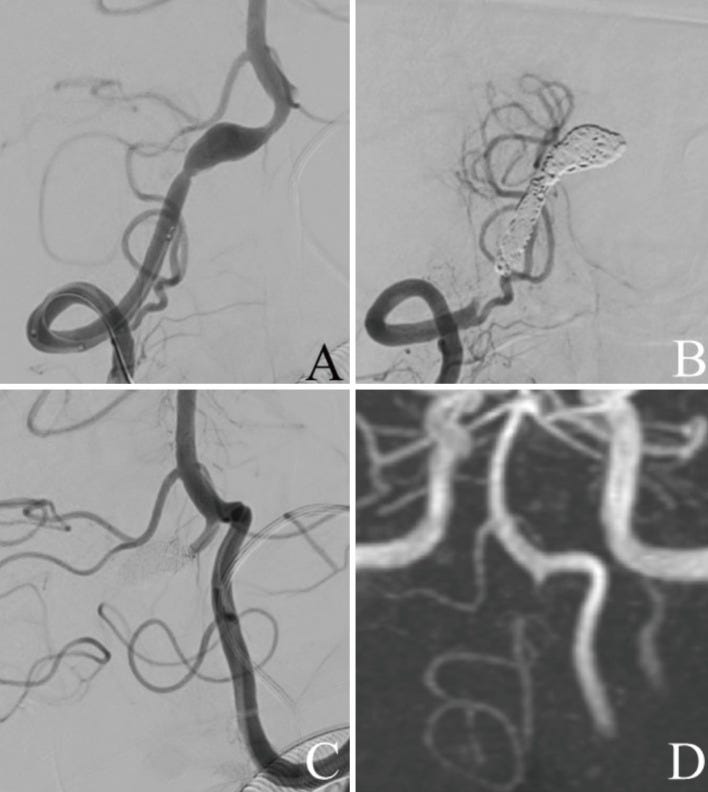

(A) Frontal view of the right vertebral artery angiography (VAG) before internal trapping shows dissecting aneurysm in the right VA. (B) Frontal view of the right VAG after internal trapping reveals that the dissecting lesion was occluded just distal to the origin of the right posterior inferior cerebellar artery (PICA). (C) Frontal view of the left VAG after internal trapping also reveals that the dissecting lesion was occluded. (D) Postoperative magnetic resonance angiography (MRA) performed 2 weeks after treatment reveals that the dissecting lesion of the right VA was not visualized.